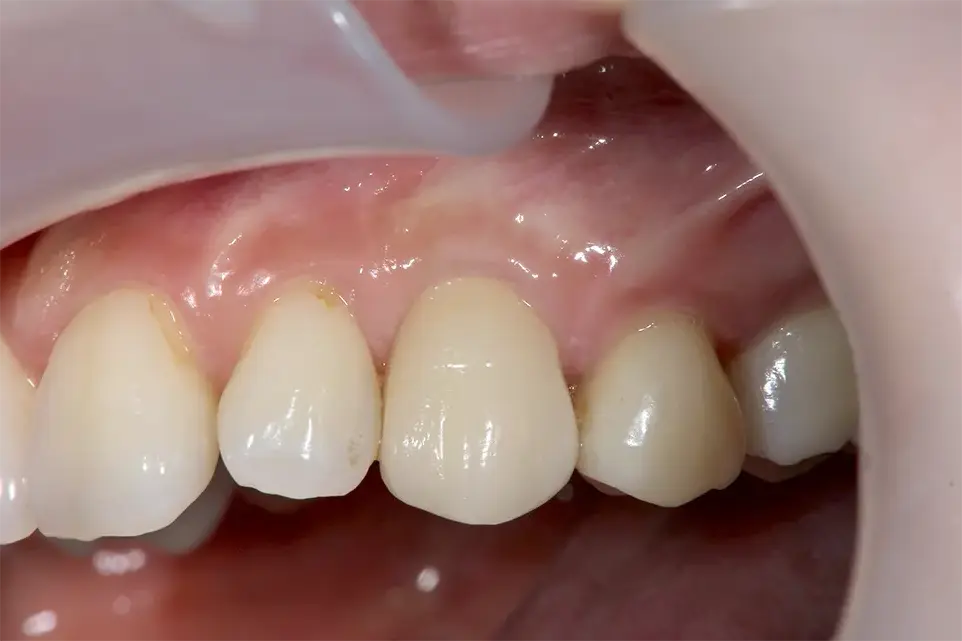

症例5

治療後

レントゲン(骨造成後)

| 患者の症状 | 今まで可撤式部分入れ歯をしていたがインプラント治療希望。他のインプラントクリニックを2件受診したが骨がないので出来ないと言われた。

視診では顕著な骨量不足は認められないがCTで精査したところ垂直的に顕著な骨量不足が認められた。 チタンメッシュによる骨造成およびインプラント治療。 |

| 治療結果 | 術後10年以上経過しているが審美的にも機能的にも非常に満足している。 |